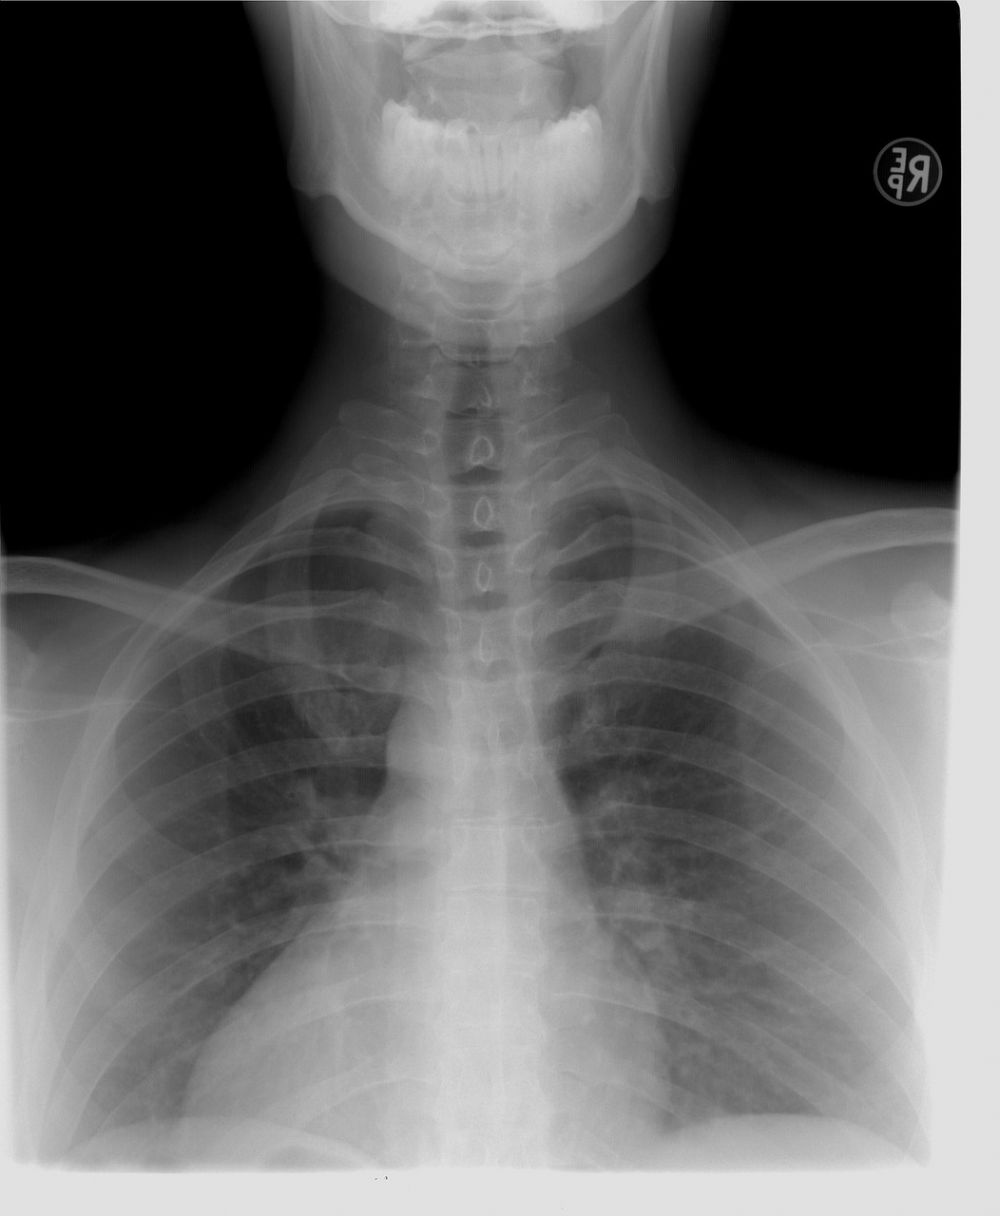

Røntgenundersøgelse

01 juni 2025